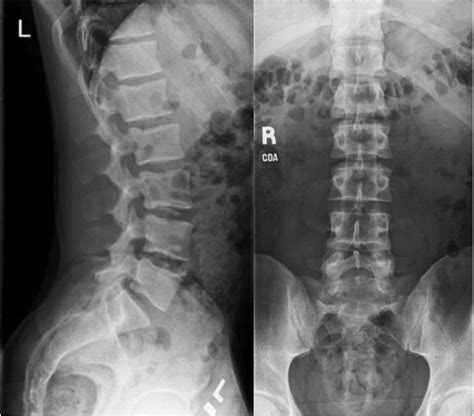

Assess the Overall Alignment: Begin by evaluating the overall alignment of the lumbar spine. Look for any signs of scoliosis, kyphosis, or lordosis. Abnormal curvatures can indicate underlying issues such as muscle imbalances, degenerative diseases, or congenital conditions. Utilize the

box to highlight standout information, such as the importance of assessing the lumbar lordosis, which is the inward curvature of the lower back.Evaluate Disc Space: The disc spaces between the vertebrae should be relatively uniform. Narrowing of the disc space can indicate degenerative disc disease, while widening may suggest ligamentous injury or infection. Use elements to compare the normal and abnormal disc spaces, providing a clear visual representation of the differences.